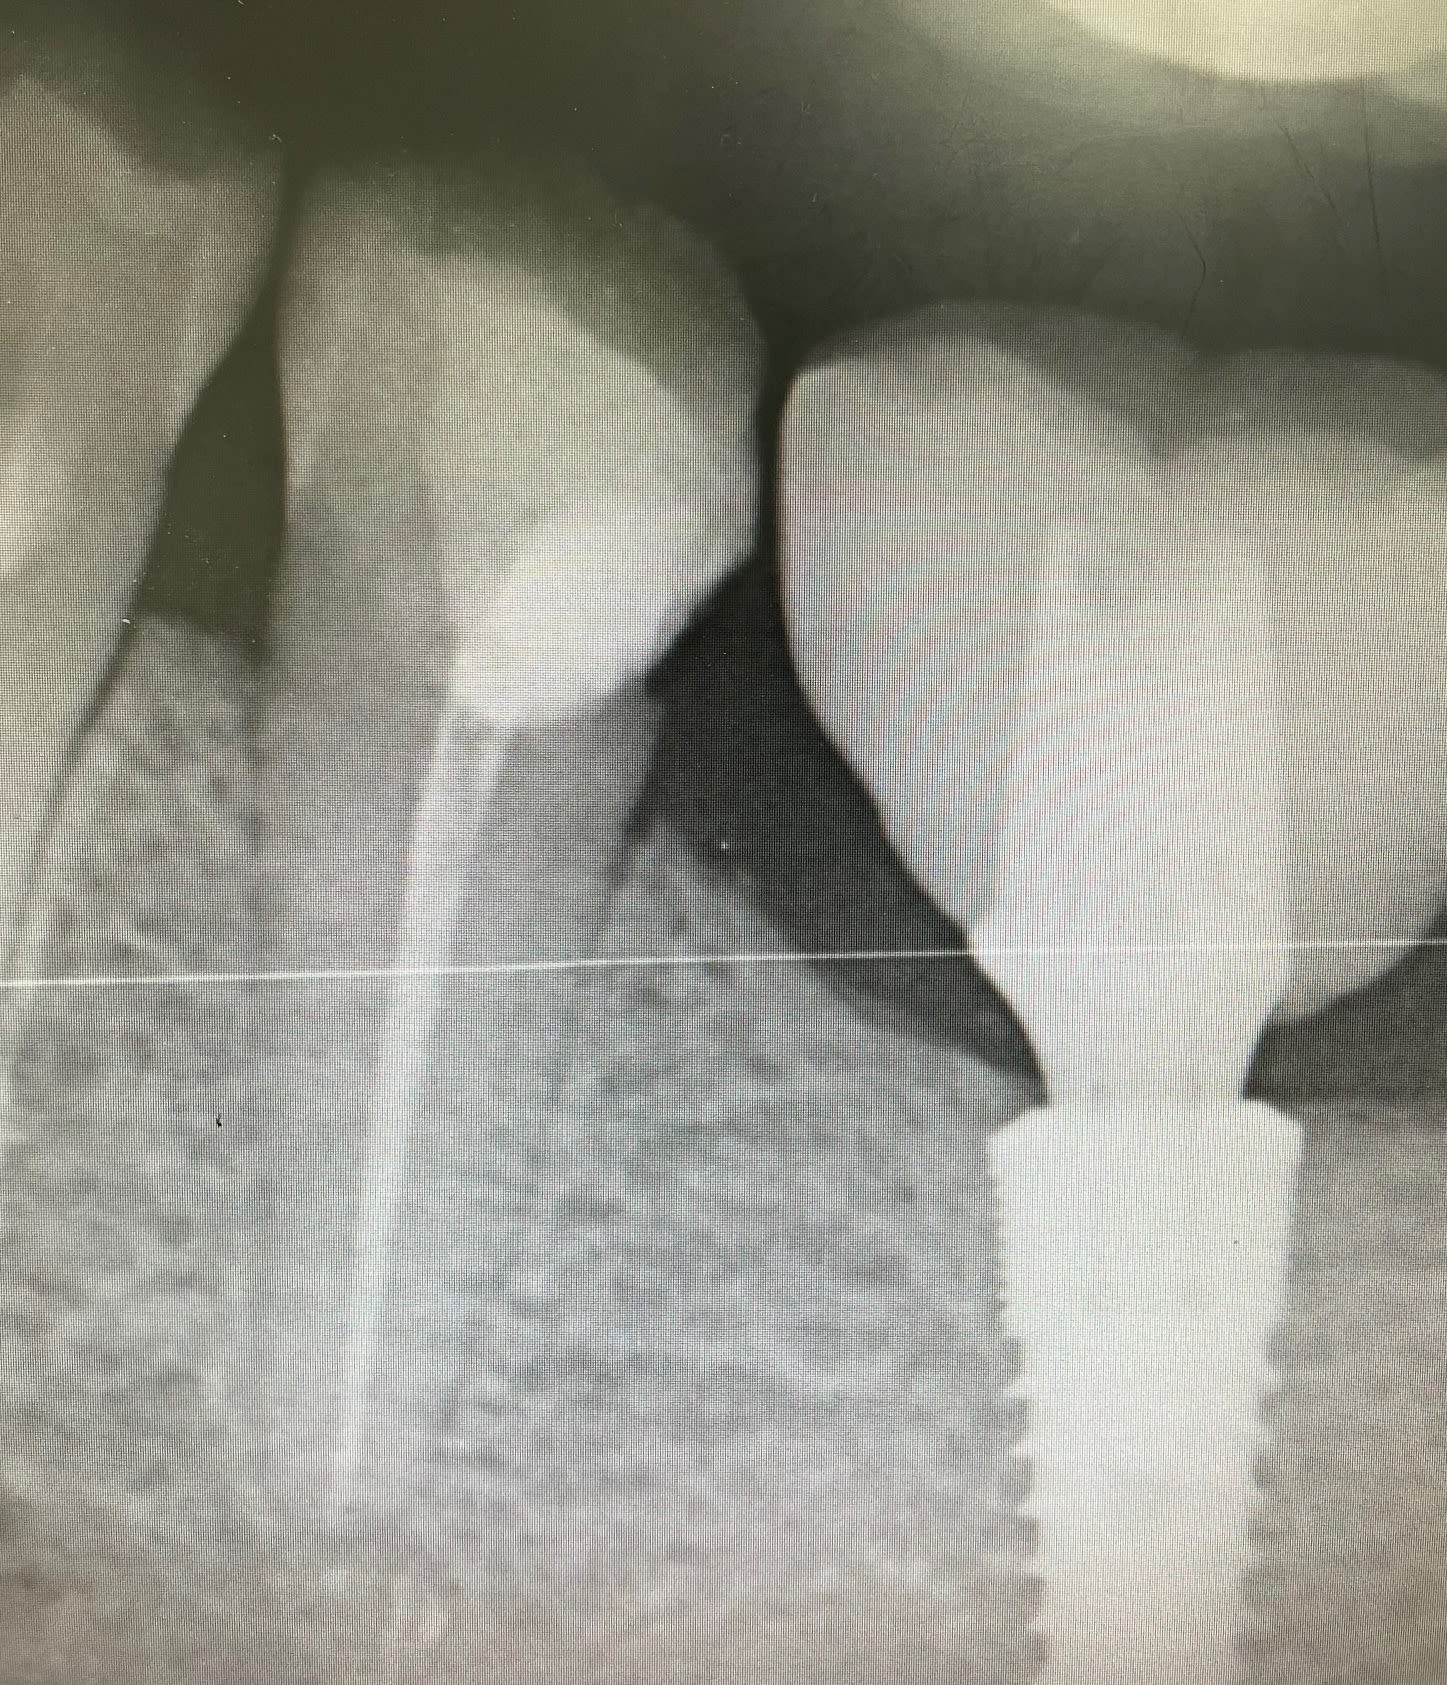

Je viens de la voir… La dent concernée est la 35. Endo en avril. Avec un compo en attente en vue de couronne. Endo faite sous digue comme toujours, obturation à chaud. C’est pas du chicot29 mais bon. Je comprendrai jamais ce besoin qu’ont certains de dénigrer le collègue pour se faire mousser. J’attends de recevoir les coordonnées de ma consœur pour passer un petit appel confraternel…( clin d’œil à JC Bonnet: l’ordre restera en dehors de tout ça, le téléphone est notre ami!)

C’est clair, ce que tu as fait c’est très propre…..une petite couronne et au top….

Il est clair que si elle trouve l’endo incorrecte, c’est qu’elle n’en fait pas, la consoeur.

Au vu de la radio.